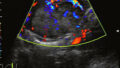

・進行すると肝硬変や肝臓がんへ進むリスクがあり、健康診断での肝機能検査や腹部超音波検査などで早期発見することが重要です。

・肝生検の代替としてFibroScanなどの非侵襲的検査がある。